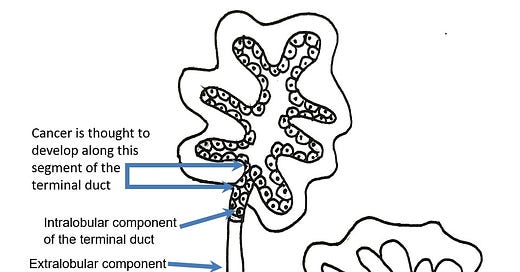

Most cases of breast cancer arise from the progenitor or stem cells of the terminal duct lobular unit, part of the normal anatomy of the female breast:

Common breast cancer types are called ductal or lobular for historical reasons - they no longer accurately reflect our understanding of their origin.